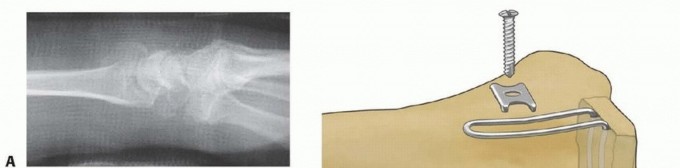

TECH FIG 7 • Volar rim fixation with a volar hook plate. A. Insertion of volar hook plate over guide pin through predrilled holes. B. Completed fixation. C. Final intraoperative x-ray showing placement of two volar hook plates into separate distal rim fragments. 1. ## Radial Column Fixation with Radial Plate 86 Expose the radial column with any of the approaches previously described. Sharply expose the interval between the first and second dorsal compartments over the tip of the radial styloid. Release the tendon sheath of the first dorsal compartment proximally, leaving the last 1 cm of tendon sheath intact. Retract the tendons of the first dorsal compartment volarly for distal exposure and dorsally for proximal exposure along the shaft. Release the terminal insertion of the brachioradialis to complete exposure of the radial column. After the initial fracture exposure, restore radial length with traction and ulnar deviation of the wrist. If needed, structural bone graft can be inserted through the radial fracture defect. Insert a 0.045-inch trans-styloid Kirschner wire angled to engage the far cortex of the proximal fragment ( TECH FIG 8A). When the advancing tip of the Kirschner wire hits the far cortex, place a drill sleeve over the Kirschner wire and use as a drill stop to limit penetration of the far cortex to 1 to 2 mm. Once the radial column is temporarily fixed with a trans-styloid Kirschner wire, reduce and stabilize other volar, dorsal, and articular fracture elements before completing fixation of the radial column.

TECH FIG 8 • Radial column fixation with radial pin plate. A. Insertion of trans-styloid Kirschner wire. B,C. Creation of pin hook. D,E. Completion and impaction of pin hook. F,G. Completed radial column fixation. Select a distal pin hole and slide a radial pin plate over the trans-styloid Kirschner wire. Proximally, guide the plate under the tendons of the first dorsal compartment and secure it initially with a single 2.3-mm bone screw. Insert a second trans-styloid Kirschner wire through a nonadjacent distal pin hole. Use the previous technique to limit penetration of the Kirschner wire through the far cortex to 1 to 2 mm. Mark a reference point where the Kirschner wire crosses the surface of the plate. Withdraw the Kirschner wire 1 cm and cut it 1 cm or more above the reference mark ( TECH FIG 8B). Position the reference mark between the lower two posts of a wire bender and create a hook ( TECH FIG 8C). By starting the bend at the reference mark, this ensures that a Kirschner wire of proper length that extends 1 to 2 mm beyond the far cortex is created. Complete the bend with a pin clamp, overbending slightly to allow the hook to snap into an adjacent pin hole or over the edge of the plate ( TECH FIG 8D). With a free 0.045-inch Kirschner wire, predrill a hole to accept the end of the hook. Impact the Kirschner wire with a pin impactor and fully seat the hook ( TECH FIG 8E). Repeat the procedure with the second Kirschner wire. Complete proximal fixation with 2.3-mm cortical bone screws ( TECH FIG 8F,G). 2. ## Radial Column Fixation with Fixed-Angle Radial Column Plate 87 Expose and reduce the radial column with the technique described previously. Position the fixed-angle radial column plate and temporarily fix with a Kirschner wire both proximally and distally ( TECH FIG 9A). Confirm reduction of the radial column and plate position with the C-arm. Using fixed-angle drill guides, drill, measure, and insert locking fixation pegs of appropriate length into the distal fixed-angle holes in the plate and standard bone screws proximally into the shaft ( TECH FIG 9B-E).